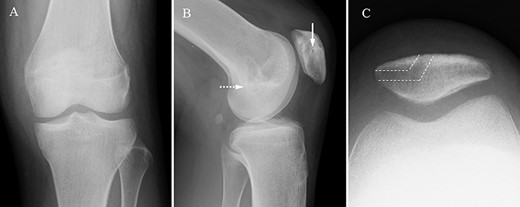

A 16-year-old female with a history of recurrent patellar dislocation underwent MPFL reconstruction surgery (Fig. 1). There was no pain nor tenderness in the medial patella, and the apprehension test was positive before surgery. Preoperative magnetic resonance imaging (MRI) showed no injury to the cartilage in the patellofemoral (PF) joint, and hypertrophic medial plica was observed. Arthroscopy showed no cartilage injury in the PF joint. For the tendon graft, a tape-type artificial ligament with a width of 15 mm (Leeds-Keio Ligament, Xiros plc, Leeds, United Kingdom) was used [2]. A bone tunnel was constructed to pass the ligament through the medial side and anterior surface of the patella, and the folded ligament was pulled into the femoral tunnel and fixed at 60° flexion with a bioabsorbable screw (BIOSURE PK Screw, Smith & Nephew Inc., Endoscopy Division, Mansfield, MA, United States). The tension pattern of the reconstructed ligament exhibited laxity under flexion and mild tension under extension. ROM exercises and partial weight-bearing were allowed at 1 week postoperatively and gradually progressed to full weight-bearing at 4 weeks postoperatively.

Radiographs of the left knee after MPFL reconstruction. Anteroposterior (A), lateral (B) and axial (C) radiographs of the left knee after MPFL reconstruction showing the entry of patella tunnel (white arrow), entry of femoral tunnel (white dot arrow) and bone tunnel of patella (white dot line). Patella tilt of post-operation was similar to that of pre-operation.